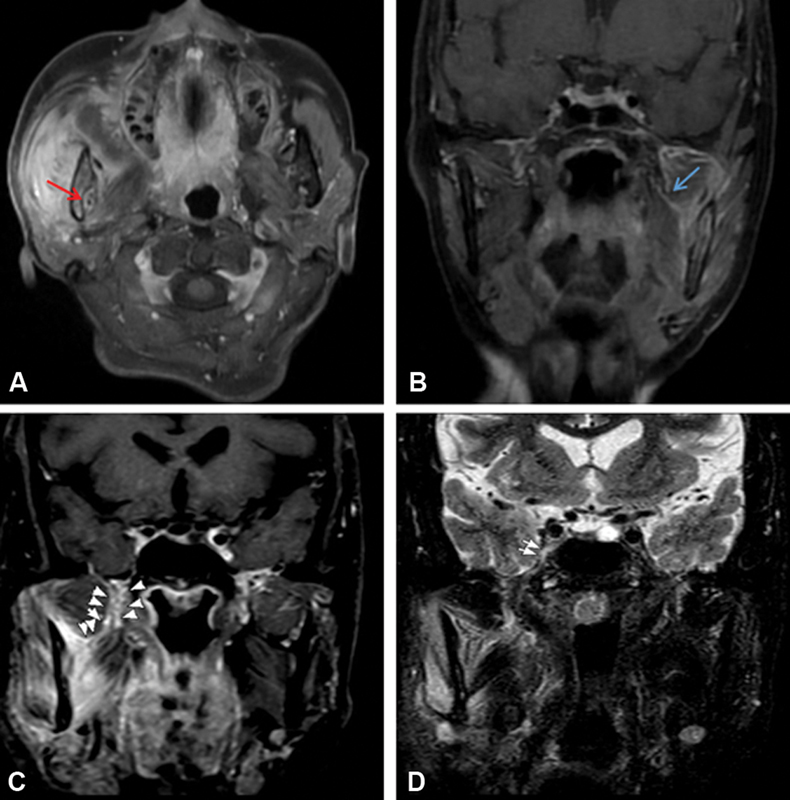

| Figure 4:(A) Axial postcontrast magnetic resonance imaging showing right upper Guillain-Barre syndrome mass with associated enhancement along right mandibular nerve in mandibular foramen suggesting perineural spread (red arrow). (B) Coronal postcontrast image showing enhancement along the infratemporal fossa component of the left mandibular (blue arrow). (C and D) Coronal postcontrast image showing enhancement and thickening of the right mandibular nerve involving foramen and suspicious intracranial extension superiorly (white arrowheads and arrow).